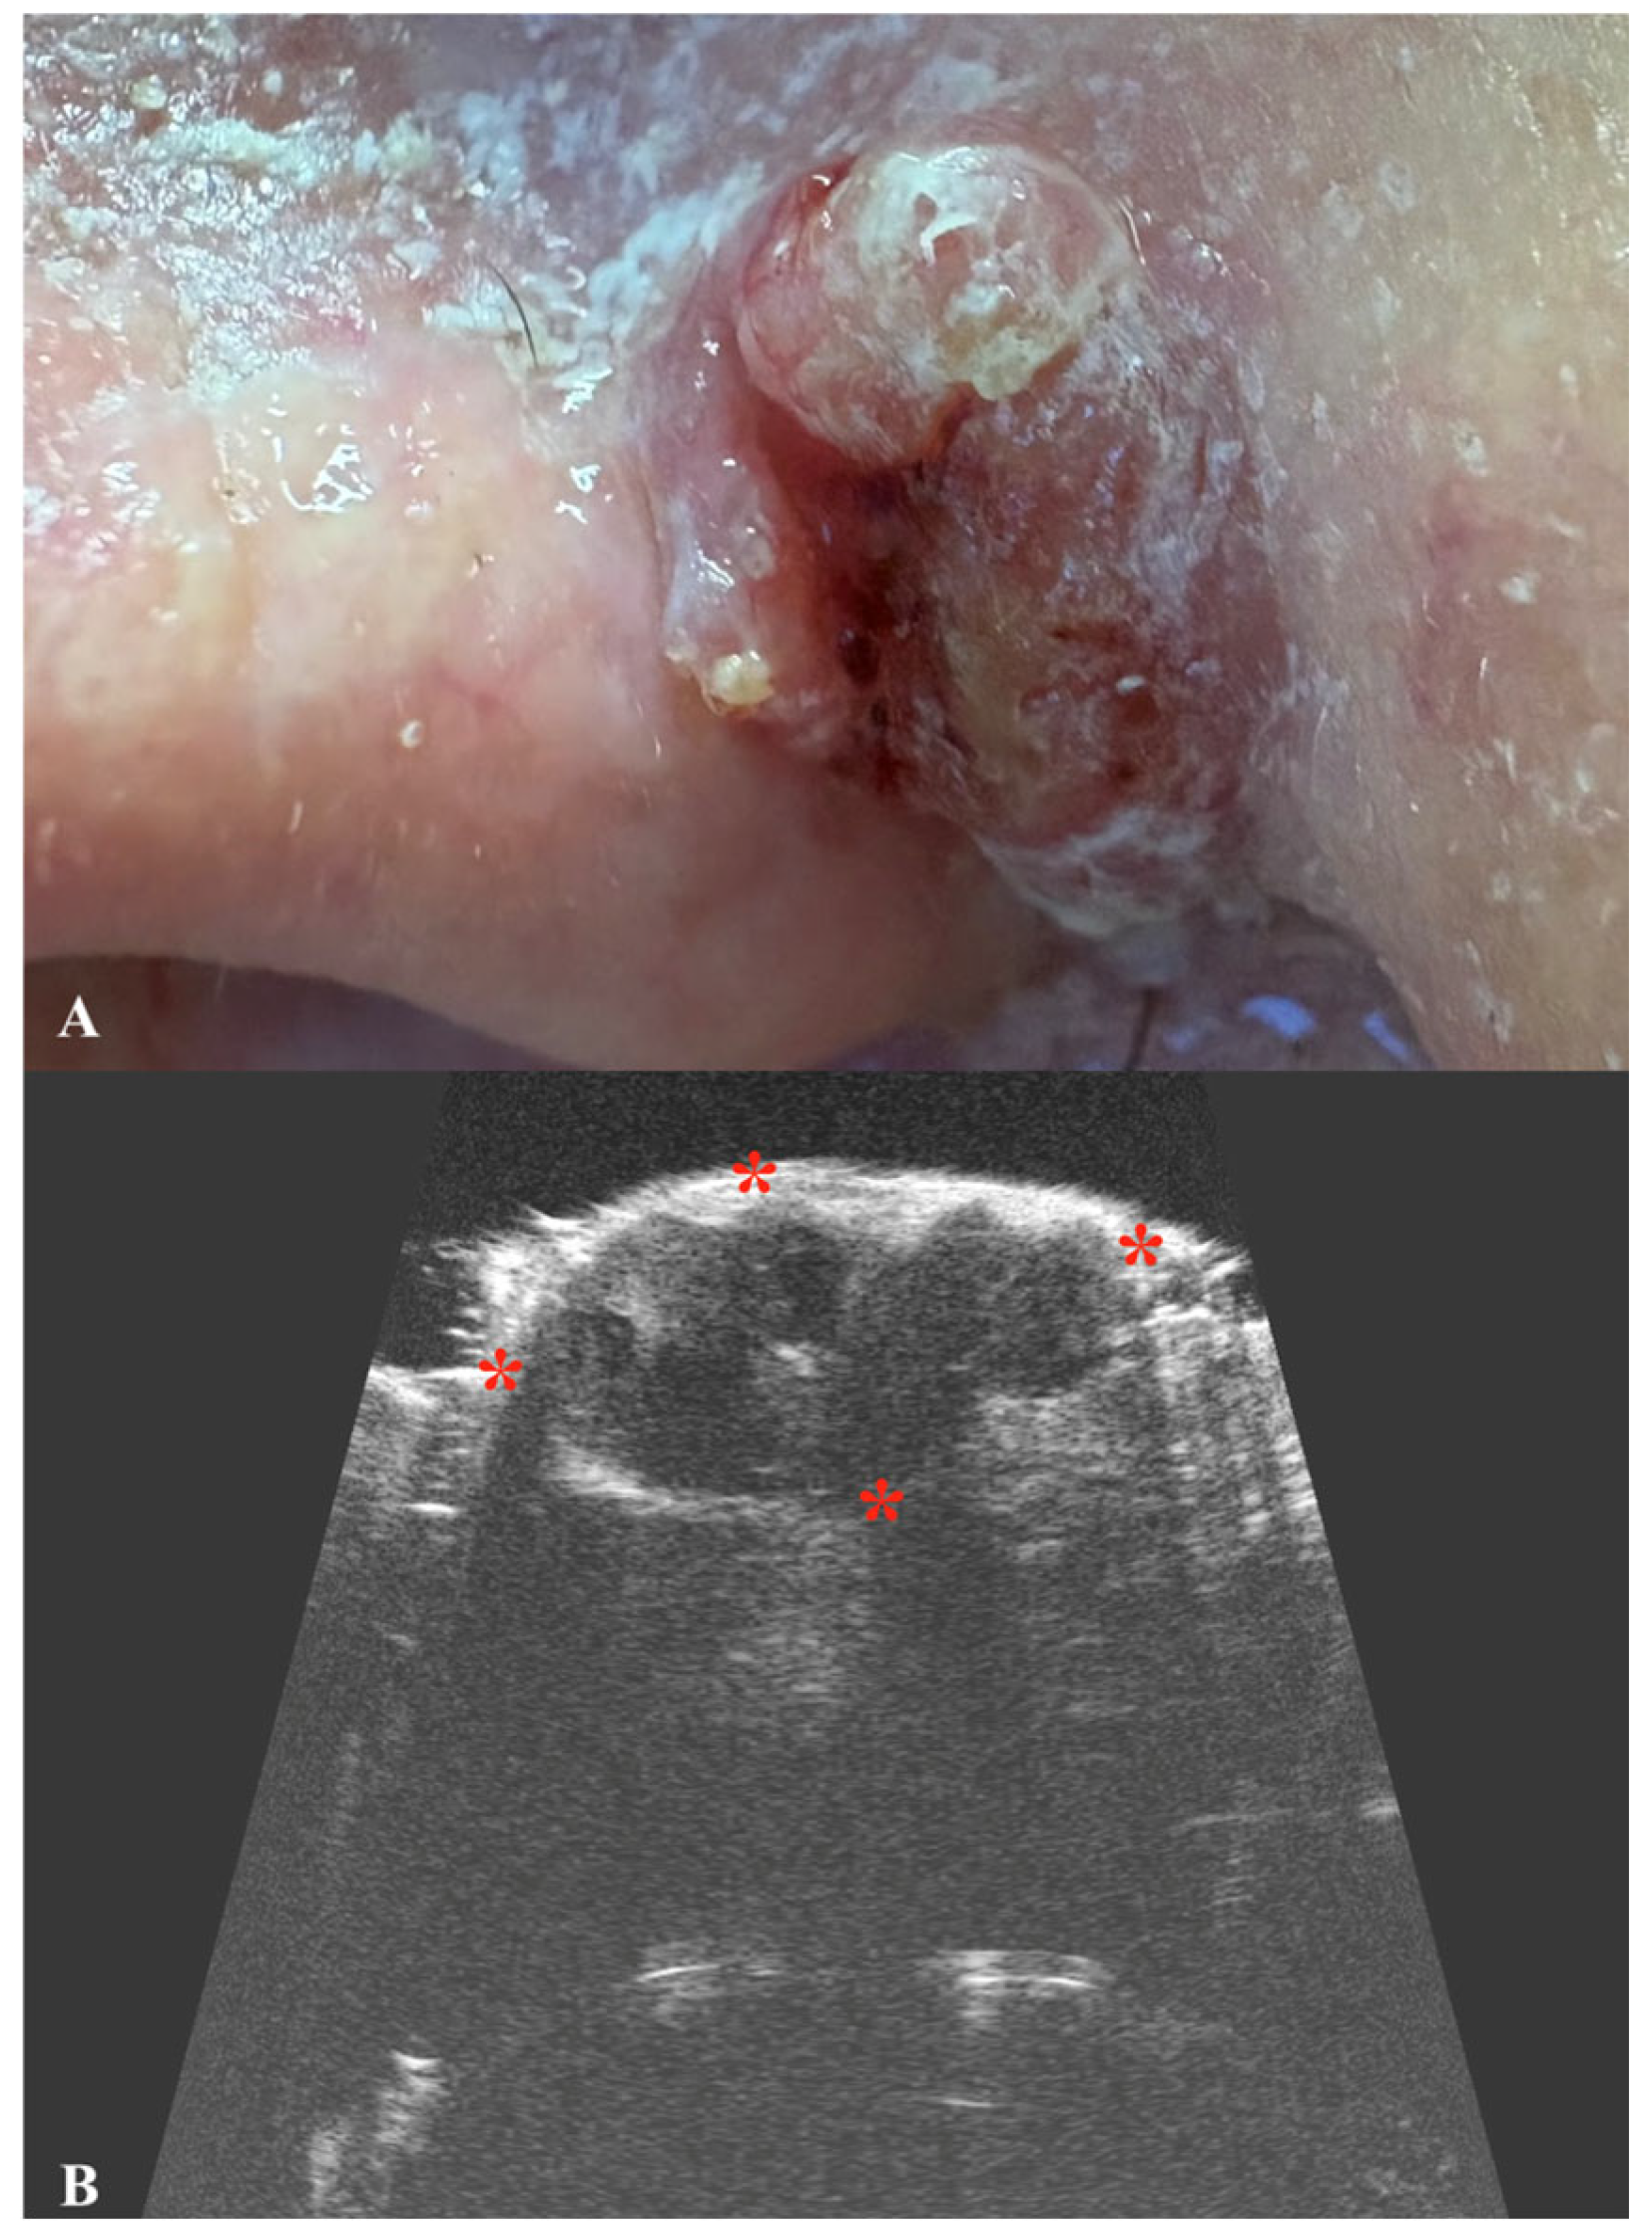

2. Basal Cell Carcinoma

| Basal Cell Carcinoma | Oval, hypoechogenic lesion with well-defined borders. Hyperechoic spots (“cotton flower” pattern) may be present. Poor vascularization on Doppler. |